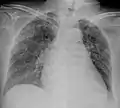

Miliary tuberculosis is a form of tuberculosis that is characterized by a wide dissemination into the human body and by the tiny size of the lesions (1–5 mm). Its name comes from a distinctive pattern seen on a chest radiograph of many tiny spots distributed throughout the lung fields with the appearance similar to millet seeds—thus the term "miliary" tuberculosis. Miliary TB may infect any number of organs, including the lungs, liver, and spleen.[2] Miliary tuberculosis is present in about 2% of all reported cases of tuberculosis and accounts for up to 20% of all extra-pulmonary tuberculosis cases.[3]

A case of miliary tuberculosis in an 82-year-old woman:

X-ray, 22 days after onset, showing extensive bilateral reticulo-nodular infiltrates